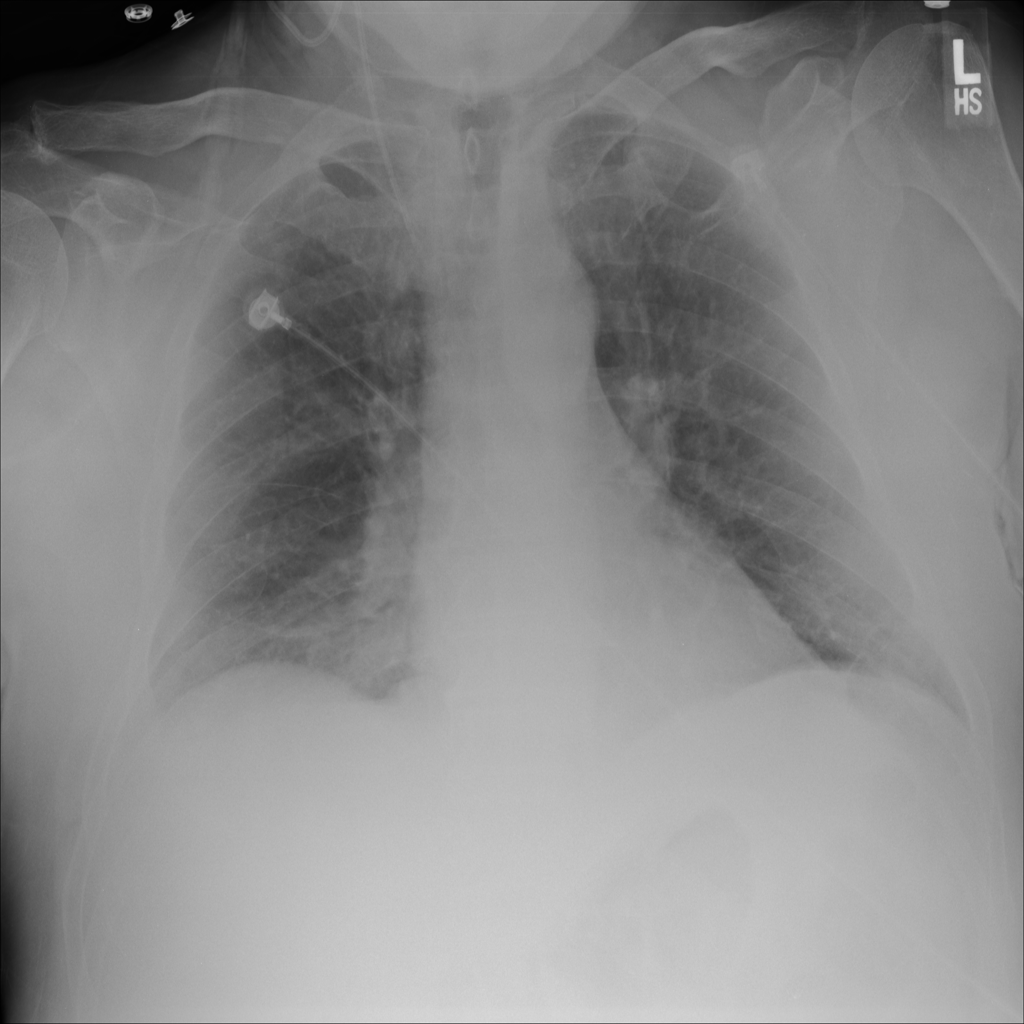

PAT-24D9 · IMG-006Edema

PAT-24D9 · IMG-006

AP